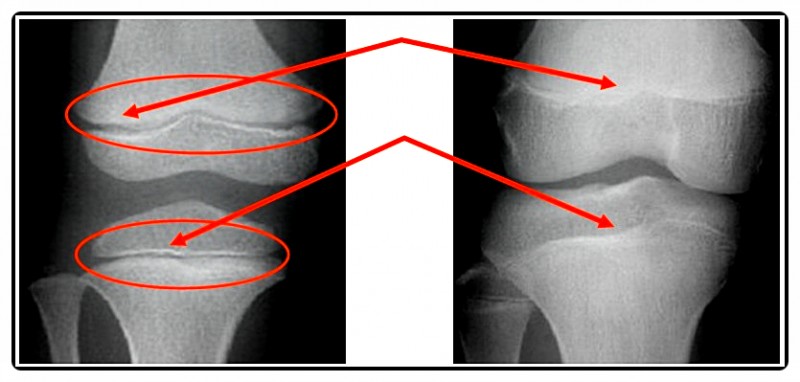

특히 성장판은 균형 잡힌 하중과 자극을 받아야 정상적으로 기능합니다.

하지만 한쪽 어깨가 처져 있거나 다리 길이가 조금이라도 다르면 이야기가 달라집니다.

몸의 무게 중심이 한쪽으로 쏠리면서 특정 성장판은 과도한 압박을 받고,

반대쪽은 자극이 부족해 성장 속도의 차이가 발생하게 되죠.

이런 상태가 지속되면 골반·무릎·척추의 균형이 어긋나면서 성장판이 고르게 자극되지 못합니다.

맞춤 깔창은 이러한 하중의 불균형을 조정해 성장판이 받는 압력을 균등하게 분산시켜 줍니다.